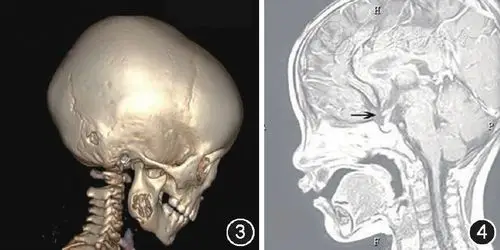

正文9,头颅ct和三维重建头颅ct扫描通常适用于既往有颅脑损伤病史

西西的头颅ct三维重建显示,面部正中巨大裂隙伴鼻骨缺失,左侧颧骨

利用3d slicer导入头颅ct,vr重建头颅模型可见头发下隆起的头皮肿物

利用3d软件对患者术前颅底ct数据进行三维重建,打印3d头颅颅骨模型

随后行患儿头颅三维重建检查(图2),并制定相应手术方案.